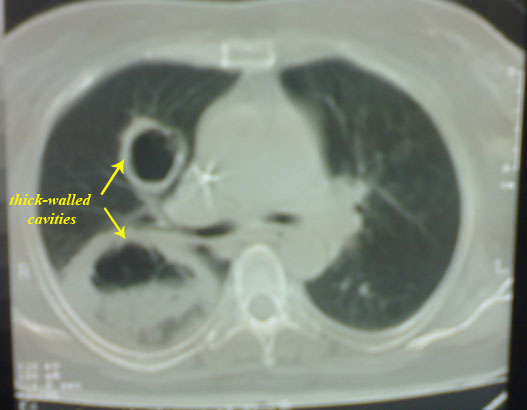

C.T. chest revealed:

-right thick-walled cavity lesion with radio-opaque shadow.

?? Aspergilloma (fungal infection with Aspergillus fumigatus). However

we sent the sputum for the studies.